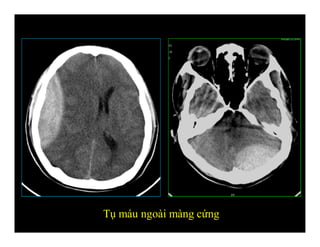

TỤ MÁU NGOÀI MÀNG CỨNG

(Epidural hematoma)

-Hình hai mặt lồi (biconvex/ lenticular)

-Không vượt qua khớp sọ

-Chạy vượt qua nếp màng não (liềm, lều

não)